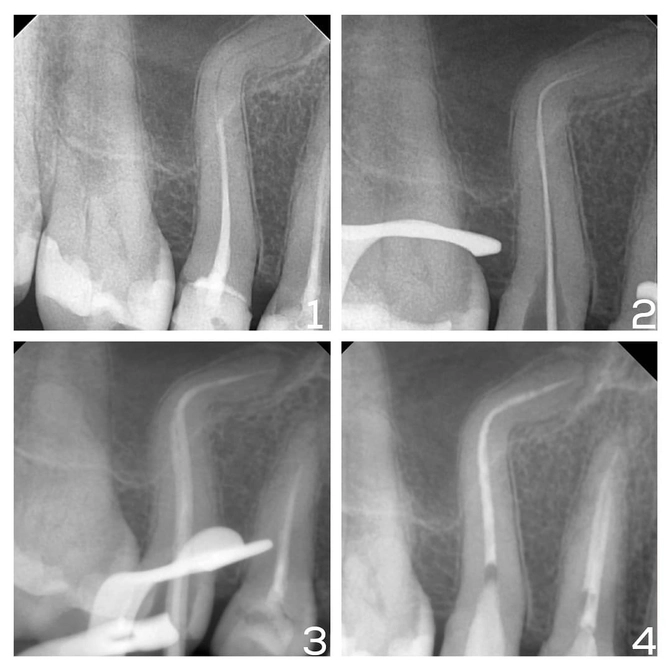

Что видим:

На "четверке" и "пятерке" несостоятельные пломбы, которые требуют замены.

Вроде пока ничего критичного.

Но на снимке видим ЭТО — корень пятого зуба изогнут в виде буквы "Г".

✔️Каналы прошли качественно и до конца, что подтверждается снимком;

✔️Запломбировали каналы биокерамическим материалом — он не вступает в реакцию с тканями зуба, совместим с дентином, не дает усадку и снижает риск повторного воспаления за счет антимикробных свойств;